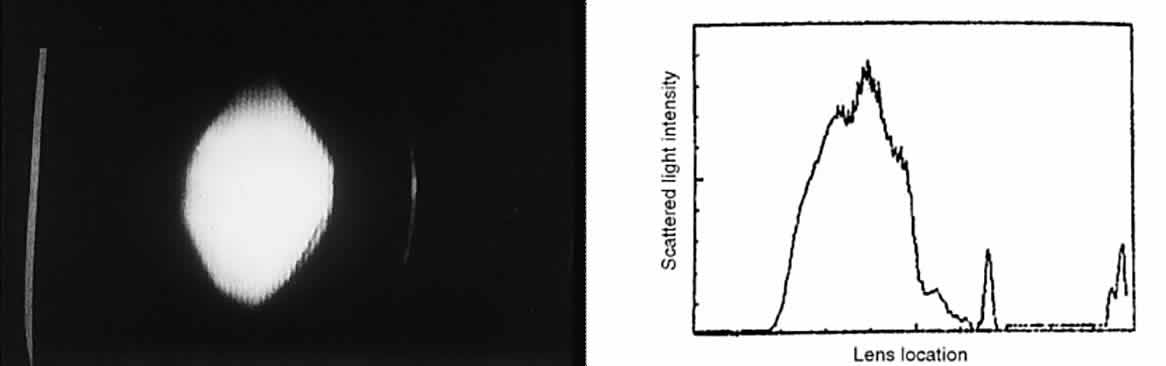

Surgical Methods When these methods fail to help a patient who has glare disability, surgical

or reduced contrast sensitivity, requires a capsulotomy. Because the

glare disability is proportional to the ratio of the area of capsule

opening over the area of capsule opacity, the size of the capsulotomy

must be considered. The size of the optimal capsulotomy equals the size

of the pupil (Fig. 11).18  Fig. 11. Top. Opaque lens capsule (note diagonal lines in capsule). Bottom. Same capsule with laser-made opening. Fig. 11. Top. Opaque lens capsule (note diagonal lines in capsule). Bottom. Same capsule with laser-made opening.